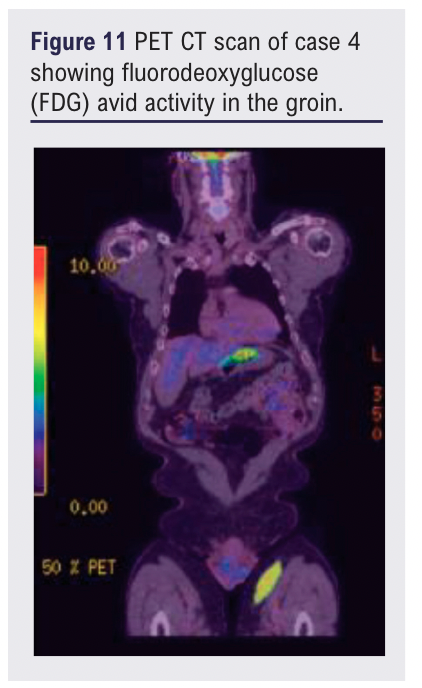

At review, in addition to the left groin mass, two lateral thigh lesions were identified. The patient was otherwise clinically well with no systemic symptoms. Subsequent MRI confirmed an 11 cm subcutaneous mass encasing the great saphenous vein without muscular invasion. A PET-CT scan showed FDG avid activity in the thigh lesions as well as the abdomen and pelvis (see Figures 11 and 12).

The role of advanced imaging modalities such as MRI and PET-CT is increasingly important when lesions exhibit atypical characteristics. PET imaging is particularly valuable in the assessment of marginal zone lymphoma and has been shown to correlate with disease burden and staging, especially in relapsed or extranodal presentations.10,11 This should be considered early in patient pathways where there is a history of adulthood haematological malignancy.